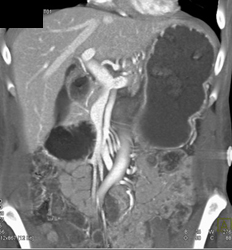

RCA Aneurysm